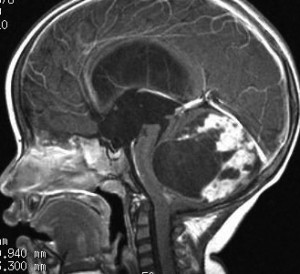

2歳の時に歩行障害で転倒しやすくなって発症しました。巨大な小脳虫部の毛様細胞性星細胞腫です。後頭下開頭で亜全摘出して,翌年,残っていた小さな残存腫瘍を全摘出しました。

cerebellarpilo3cerebellarpilo4

16歳になってとても元気に学校へ通っています。こんな小脳でもちゃんと歩けるようになります。残っているわずかな小脳機能を手術で守ることはとても難しいと言えます。